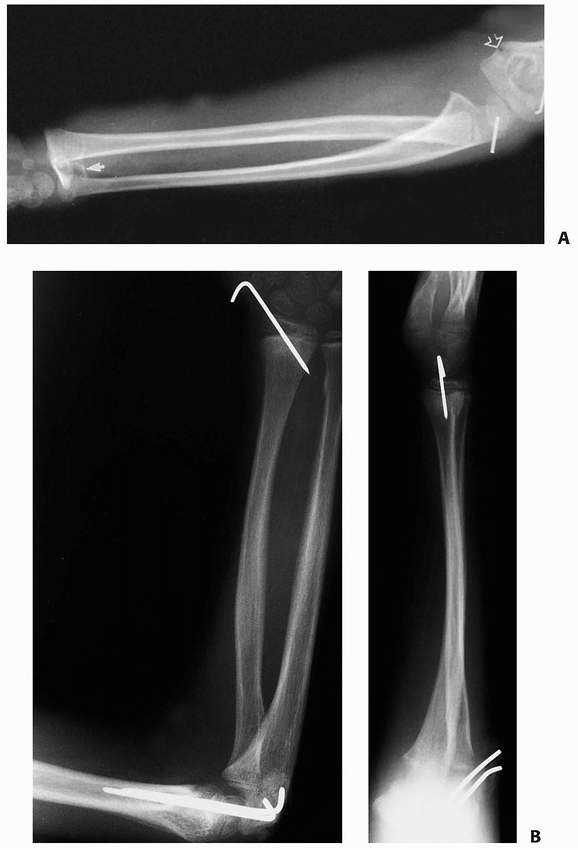

![]() |

|

FIGURE 9-31 A,B. A 10-year-old boy sustained a closed Salter-Harris type I separation of the distal ulnar physis (arrows) combined with a fracture of the distal radial metaphysis. C. An excellent closed reduction was achieved atraumatically. D. Long-term growth arrest of the distal ulna occurred.

FIGURE 9-32 A. The appearance of the distal ulna in the patient seen in Figure 9-21,

3 years after injury, demonstrating premature fusion of the distal ulnar physis with 3.2 cm of shortening. The distal radius is secondarily deformed, with tilting and translocation toward the ulna. B. In the patient in Figure 9-21 with distal ulnar physeal arrest, a lengthening of the distal ulna was performed using a small unipolar distracting device. The ulna was slightly overlengthened to compensate for some subsequent growth of the distal radius. C. Six months after the lengthening osteotomy, there is some deformity of the distal ulna, but good restoration of length has been achieved. The distal radial epiphyseal tilt has corrected somewhat, and the patient has asymptomatic supination and pronation to 75 degrees. D. Similar case to Figure 9-32A-C, but with more progressive distal radial deformity treated with corrective osteotomy and epiphysiodesis of the distal radius. |

deformity. Treatment involves rebalancing the length of the radius and

ulna. The options include hemiphyseal arrest of the radius, corrective

radial closing wedge osteotomy, and ulnar lengthening (Fig. 9-32),12,81,152

or a combination of these procedures. The painful impingement of the

radius and ulna with forearm rotation can be corrected with

reconstitution of the distal radioulnar joint. If the radial physis has

significant growth remaining, a radial physeal arrest should be done at

the same time as the surgical rebalancing of the radius and ulna.154 Treatment is individualized depending on the age of the patient, degree of deformity, and level of pain and dysfunction.